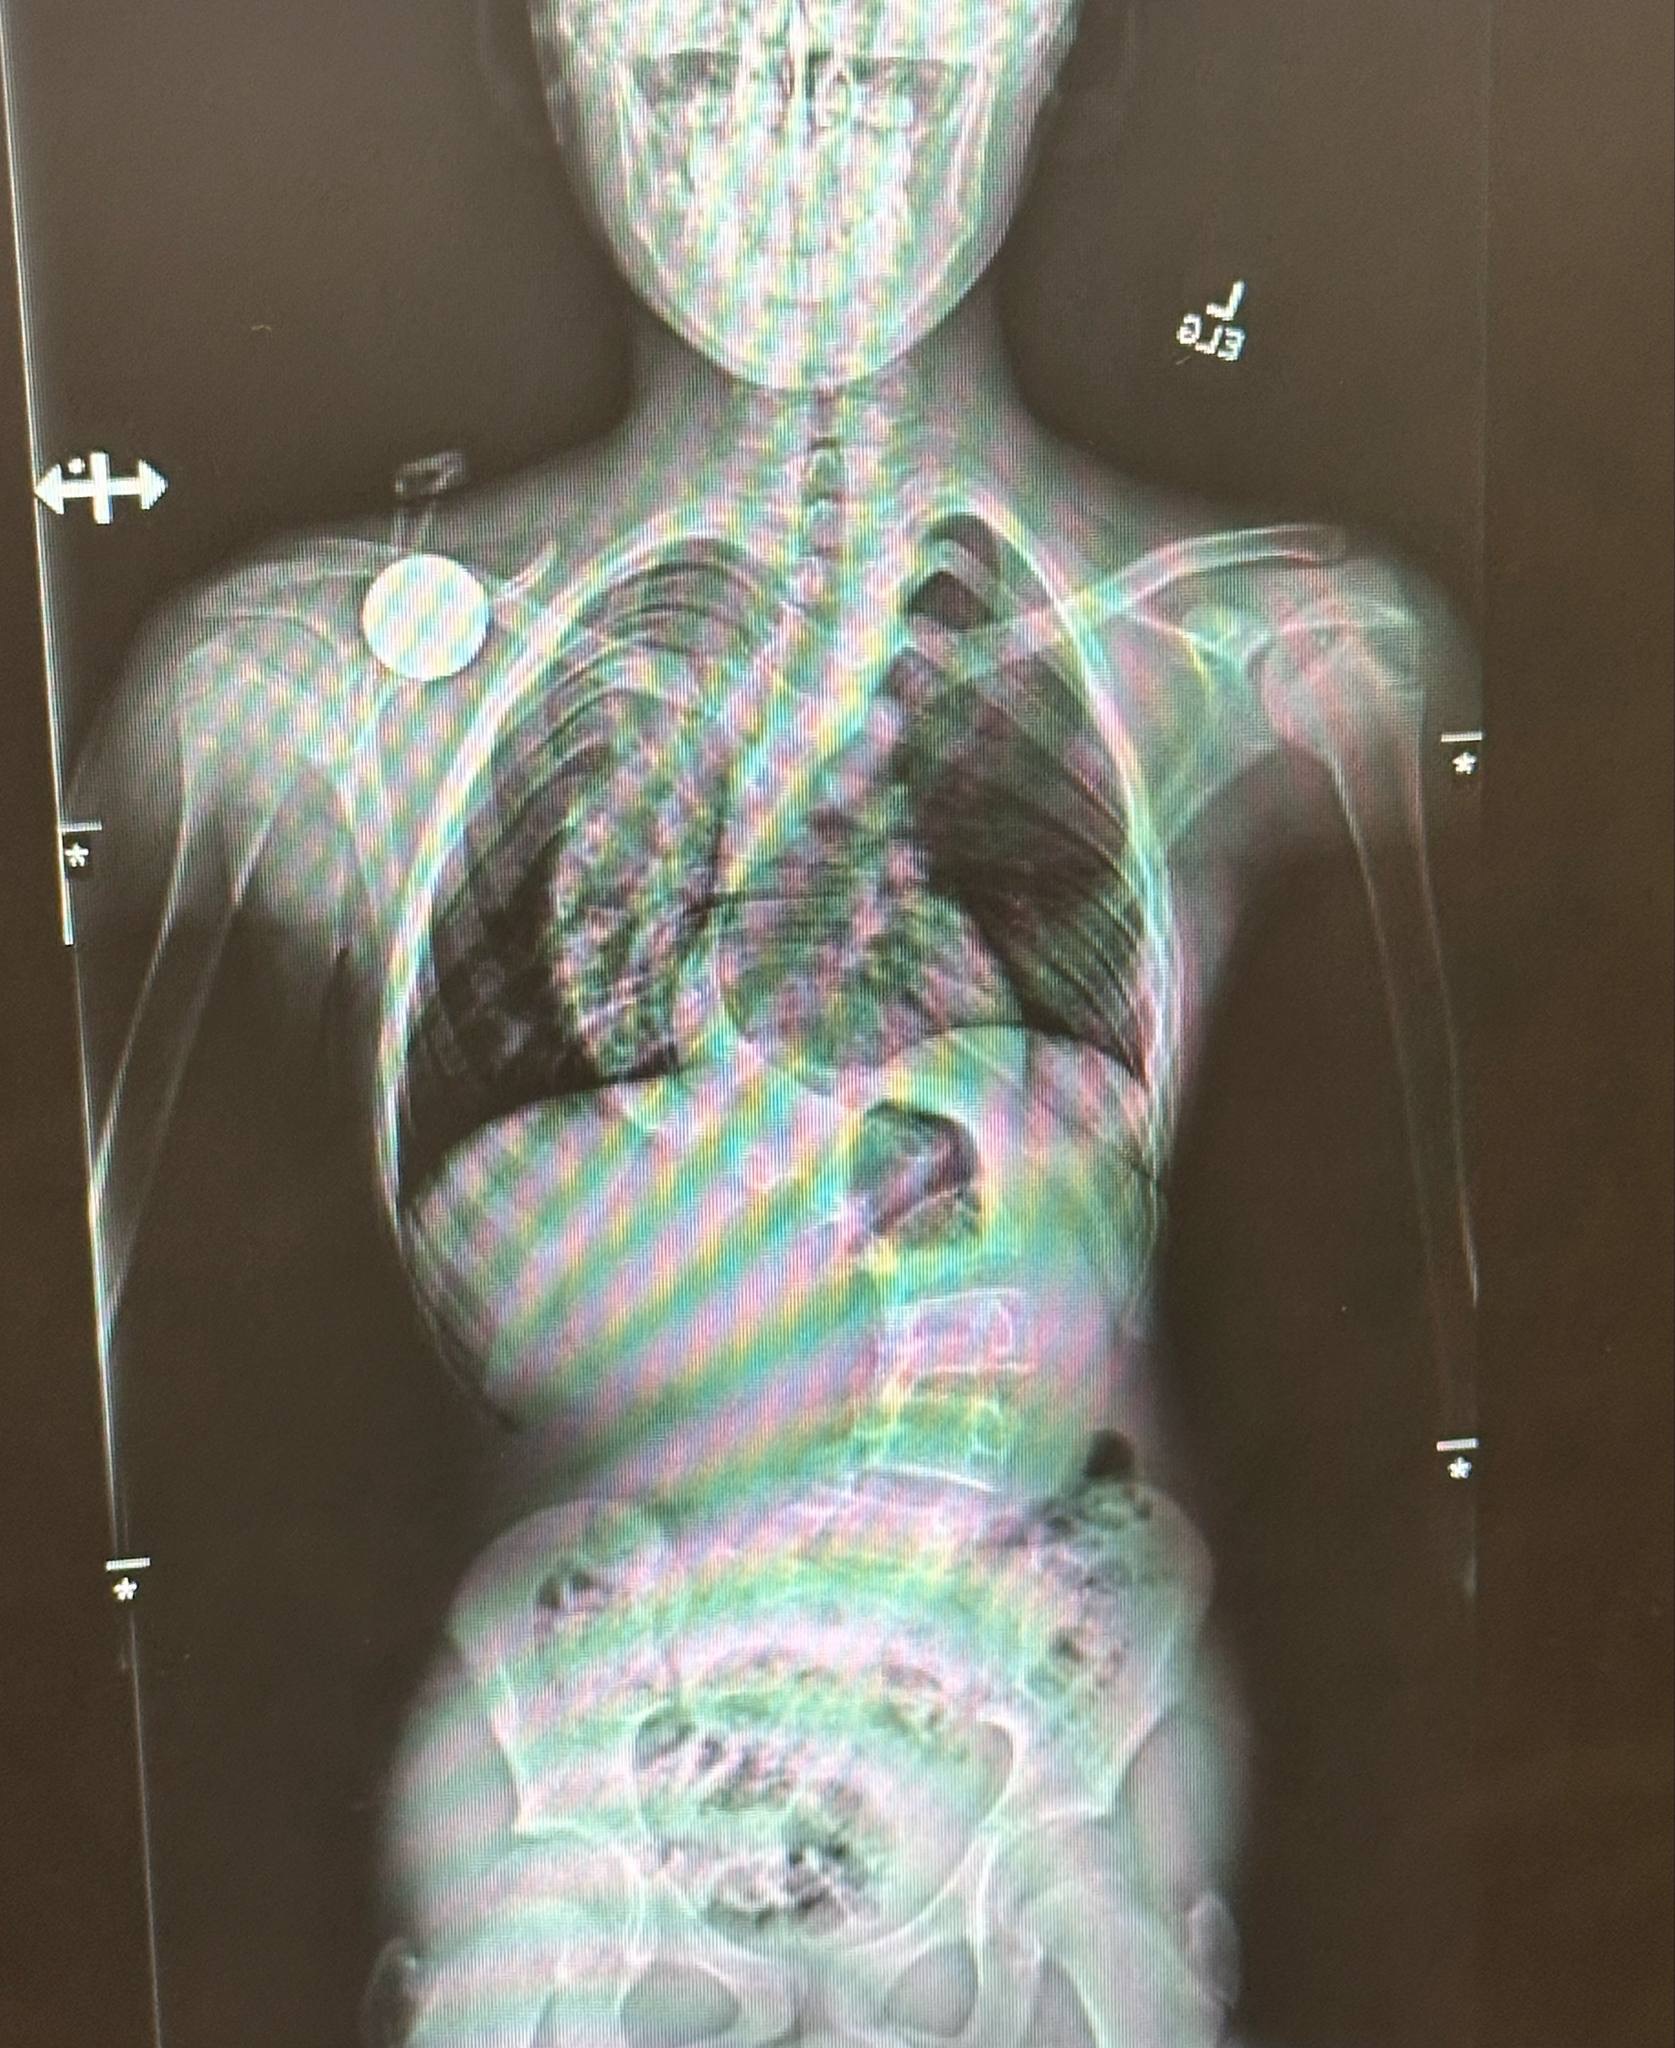

I’m reaching out today on behalf of my brave nephew who is facing a battle no child should have to endure — severe scoliosis. His spine has curved so significantly that it’s affecting his posture, mobility, and even his breathing. After months of consultations, specialists have determined that surgery is urgently needed to prevent long-term complications and give him a chance at a full, healthy life.